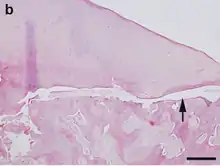

برغم كثرة البحوث، إلا أن الأسباب لاتزال غير واضحة، ولكن قد تشمل الصدمة الجسدية المتكررة، والإسكيمية ( تقييد تدفق الدم )، أو ممكن أن تكون وراثية، وكما أن عوامل الغدد الصماء قد تكون سبب، والنخر الوعائي ( فقدان تدفق الدم )، و نقص النمو السريع، وعدم التوازن في نسبة الكالسيوم بالنسبة للفسفور، ومشاكل تكوين العظام.[11][12][13][14] على الرغم من أن أسم المرض " التهاب العظم والغضروف السالخ " يوحي إلى الالتهاب، إلى أنه لا توجد خلايا التهابية في الفحص النسيجي وهذا يشير إلى وجود سبب أخر غير الالتهاب. ويعتقد بأن الصدمات الصغيرة المتكررة التي تؤدي إلى كسور صغيرة وأحيانا أنقطاع وصول الدم إلى العظم الموجود تحت الغضروف قد يسببان إلى فقدان وصول الدم إلى تلك المناطق أو تغير في النمو.[15]

التهاب العظم والغضروف السالخ (التهاب عظمي غضروفي) التهاب العظم والغضروف السالخ هو اضطراب المفصل الذي يشكل الشقوق في الغضروف المفصلي والعظام تحت الغضروف الأساسي,[2] وعادة ما يسبب التهاب العظم والغضروف السالخ الألم وتورم في المفصل المصاب الذي يمسك والأقفال أثناء الحركة. والفحص البدني عادة ما يكشف عن الانصباب، والطراوة، وصوت طقطقة مع حركة المفاصل. ويسبب ايضا نقص الدم في العظام تحت الغضروف. وهذه الخسارة من تدفق الدم العظم تحت الغضروف تؤدي للموت في عملية تسمى نخر اوعائي. ثم يتم استيعاب العظم من الجسم، وترك الغضروف المفصلي بدعم عرضه للضرر، والنتيجة هي تجزئة (تشريح) لكل من الغضاريف والعظام، وحرية حركة هذه العظام وشظايا الغضاريف ضمن مساحة المفصل، مما يسبب الألم ومزيد من الضرر.[3][4] التهاب العظم والغضروف السالخ ممكن أن يكون من الصعب تشخيصه لأن هذه الأعراض وجدت مع أمراض أخرى. ومع ذلك، فإنه من الممكن أن يضح المرض من خلال الأشعة السينية أوالأشعة المقطعية أو التصوير بالرنين المغناطيسي.